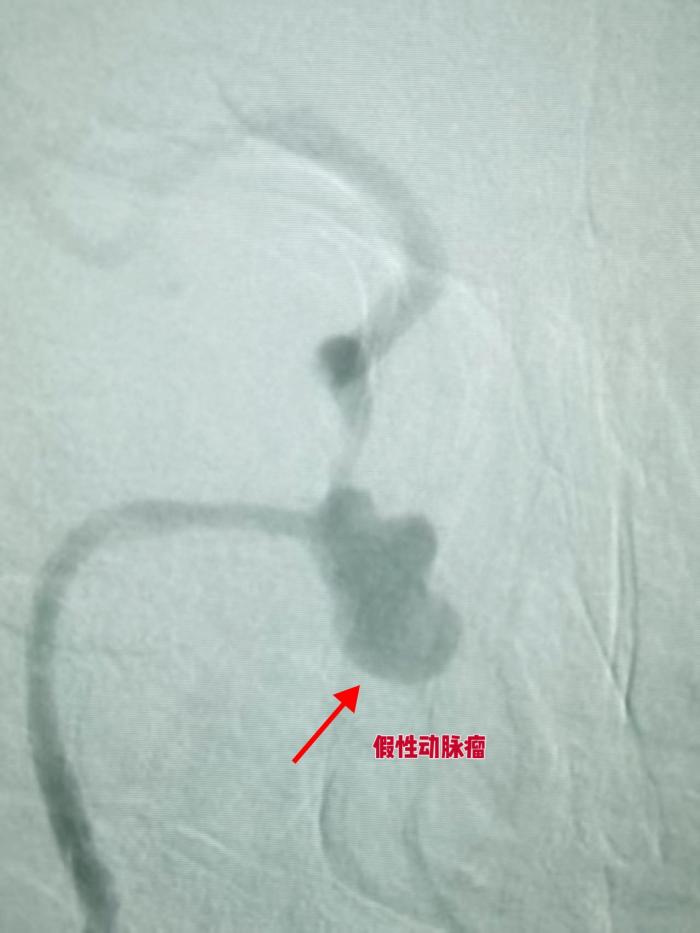

患者已被双侧鼻腔反复出血困扰一月有余,10小时前出血突然加重,紧急鼻孔填塞后仍无法止血,病情危重到随时可能因窒息殒命。血管介入外科龙文兴副主任医师火速会诊,结合患者鼻咽癌放疗病史,精准判断其为颈内动脉假性动脉瘤破裂出血。

术中造影结果让所有人捏了一把汗,患者右侧颈内动脉 C1-C4 段存在长段重度狭窄,C3 段还形成了巨大假性动脉瘤。更危险的是,动脉高压的持续冲击让瘤体较术前 CTA 检查明显增大膨出,形态愈发不规则,破裂风险已箭在弦上,而患者鼻腔仍在不断涌出鲜红色血液。

介入治疗的极速高效在此刻体现得淋漓尽致。在龙文兴医生的精准操作下,手术材料与栓塞用弹簧圈如同被赋予了生命,通过针眼大小的创口直达病灶,这种精准微创的特点,既避免了大开刀带来的二次创伤,又能让治疗直达核心。短短30多分钟,手术团队忙而不乱,一道道医嘱精准下达,一个个操作一气呵成。当最后一枚弹簧圈到位,复查造影显示假性动脉瘤未再显影,造影剂无外溢,患者鼻腔出血彻底停止,这场生死竞速,以医生的胜利告终。